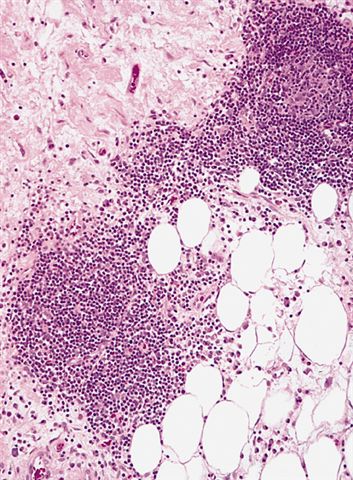

Microscopic (histologic) description

- Depends on subtype, generally composed of mature fat with variably sized adipocytes and bands of fibrotic stroma containing spindle cells with enlarged, hyperchromatic nuclei

- Can be markedly atypical

- Cellularity is low and mitotic figures are uncommon

- Atypical cells are more commonly found in fibrous septa and in a perivascular distribution

- Lipoma-like subtype

- Most common subtype

- Scattered atypical cells may be diffuse or exceedingly rare

- Frequently contains lipoblasts

- Grossly, can be indistinguishable from lipoma

- Sclerosing subtype

- Second most common subtype

- Predilection for retroperitoneal or paratesticular location

- Collagenous fibrous tissue with scattered adipocytes and atypical multinucleated stromal cells

- Scant lipogenic component may be missed in small samples

- Inflammatory subtype

- Rare

- Almost always in the retroperitoneum where it is confused with nonlipogenic tumors

- Chronic inflammatory cells (B > T cells) with occasional lymphoid follicles scattered in a cellular fibrocollagenous stroma with sparse multinucleated atypical cells

- May obscure adipocytes

Microscopic (histologic) images

Contributed by Michael Clay, M.D., Melanie Bourgeau, M.D. and AFIP

Morphologic variability: